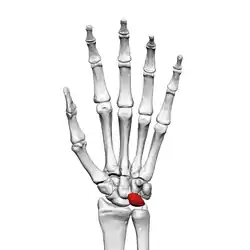

Left hand anterior view (palmar view). Lunate bone shown in red.

The lunate bone (semilunar bone) is a carpal bone in the human hand. It is distinguished by its deep concavity and crescentic outline. It is situated in the center of the proximal row carpal bones, which lie between the ulna and radius and the hand. The lunate carpal bone is situated between the lateral scaphoid bone and medial triquetral bone.

The lunate is a crescent-shaped carpal bone found within the hand. The lunate is found within the proximal row of carpal bones. Proximally, it abuts the radius. Laterally, it articulates with the scaphoid bone, medially with the triquetral bone, and distally with the capitate bone. The lunate also articulates on its distal and medial surface with the hamate bone.[2]:708[3]

The proximal surface of the lunate bone is smooth and convex, articulating with the radius. The lateral surface is flat and narrow, with a crescentic facet for articulation with the scaphoid bone. The medial surface possesses a smooth and quadrilateral facet for articulation with the triquetral bone. The palmar surface is rough, as is the dorsal surface. The dorsal surface is broad and rounded. The distal surface of the bone is deep and concave.[4]